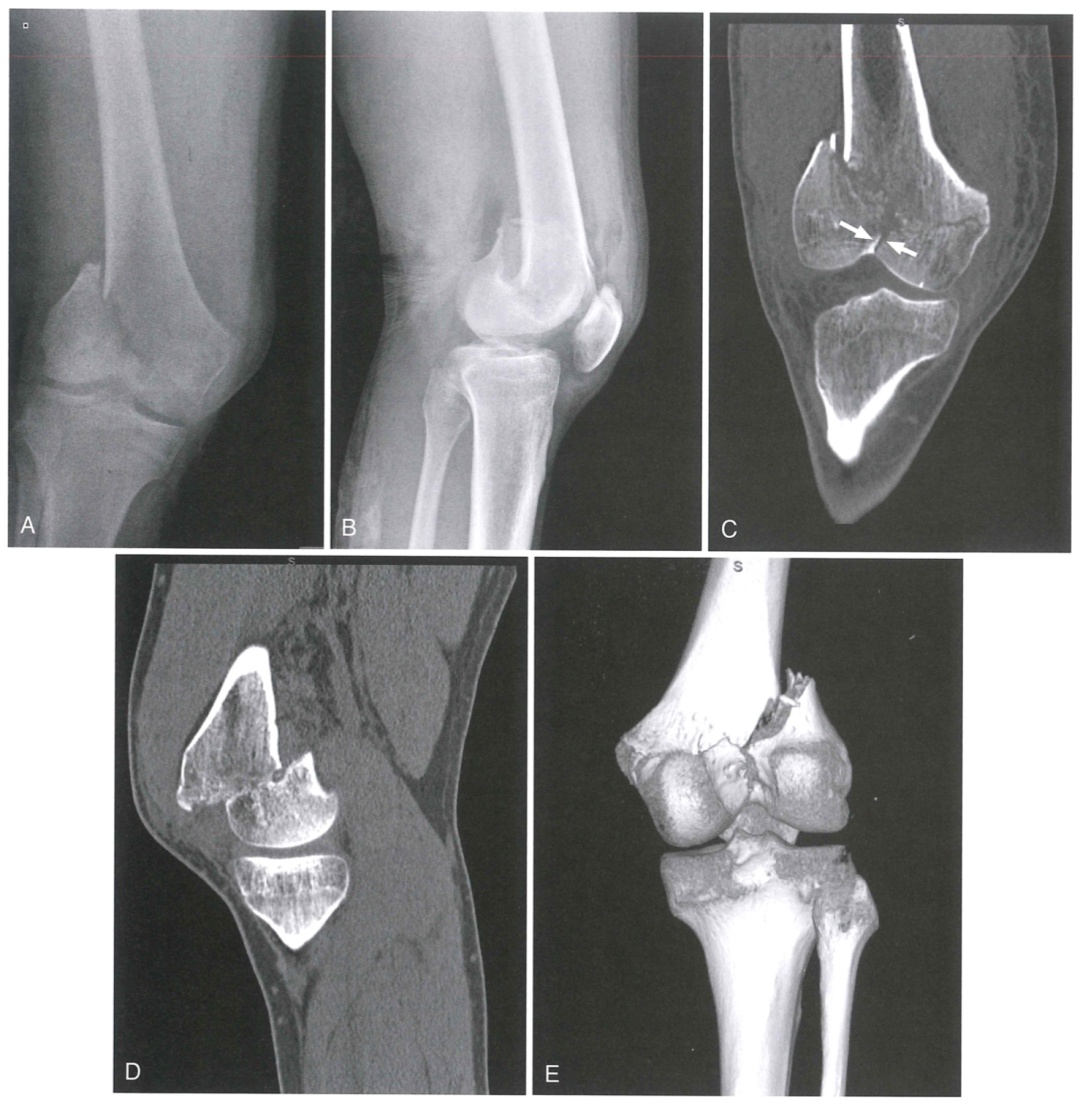

图 1 严重的骨折并不难看出来

如果真的是一不小心把骨头给摔得稀碎,通过X线和CT检查就能很容易地看出来。别说是医生,相信大家都能看出来这骨头碎成一片片了。不过,不少人的膝关节明明没骨折,怎么还是那么痛?这个时候可能就要请你去做个MRI啦!